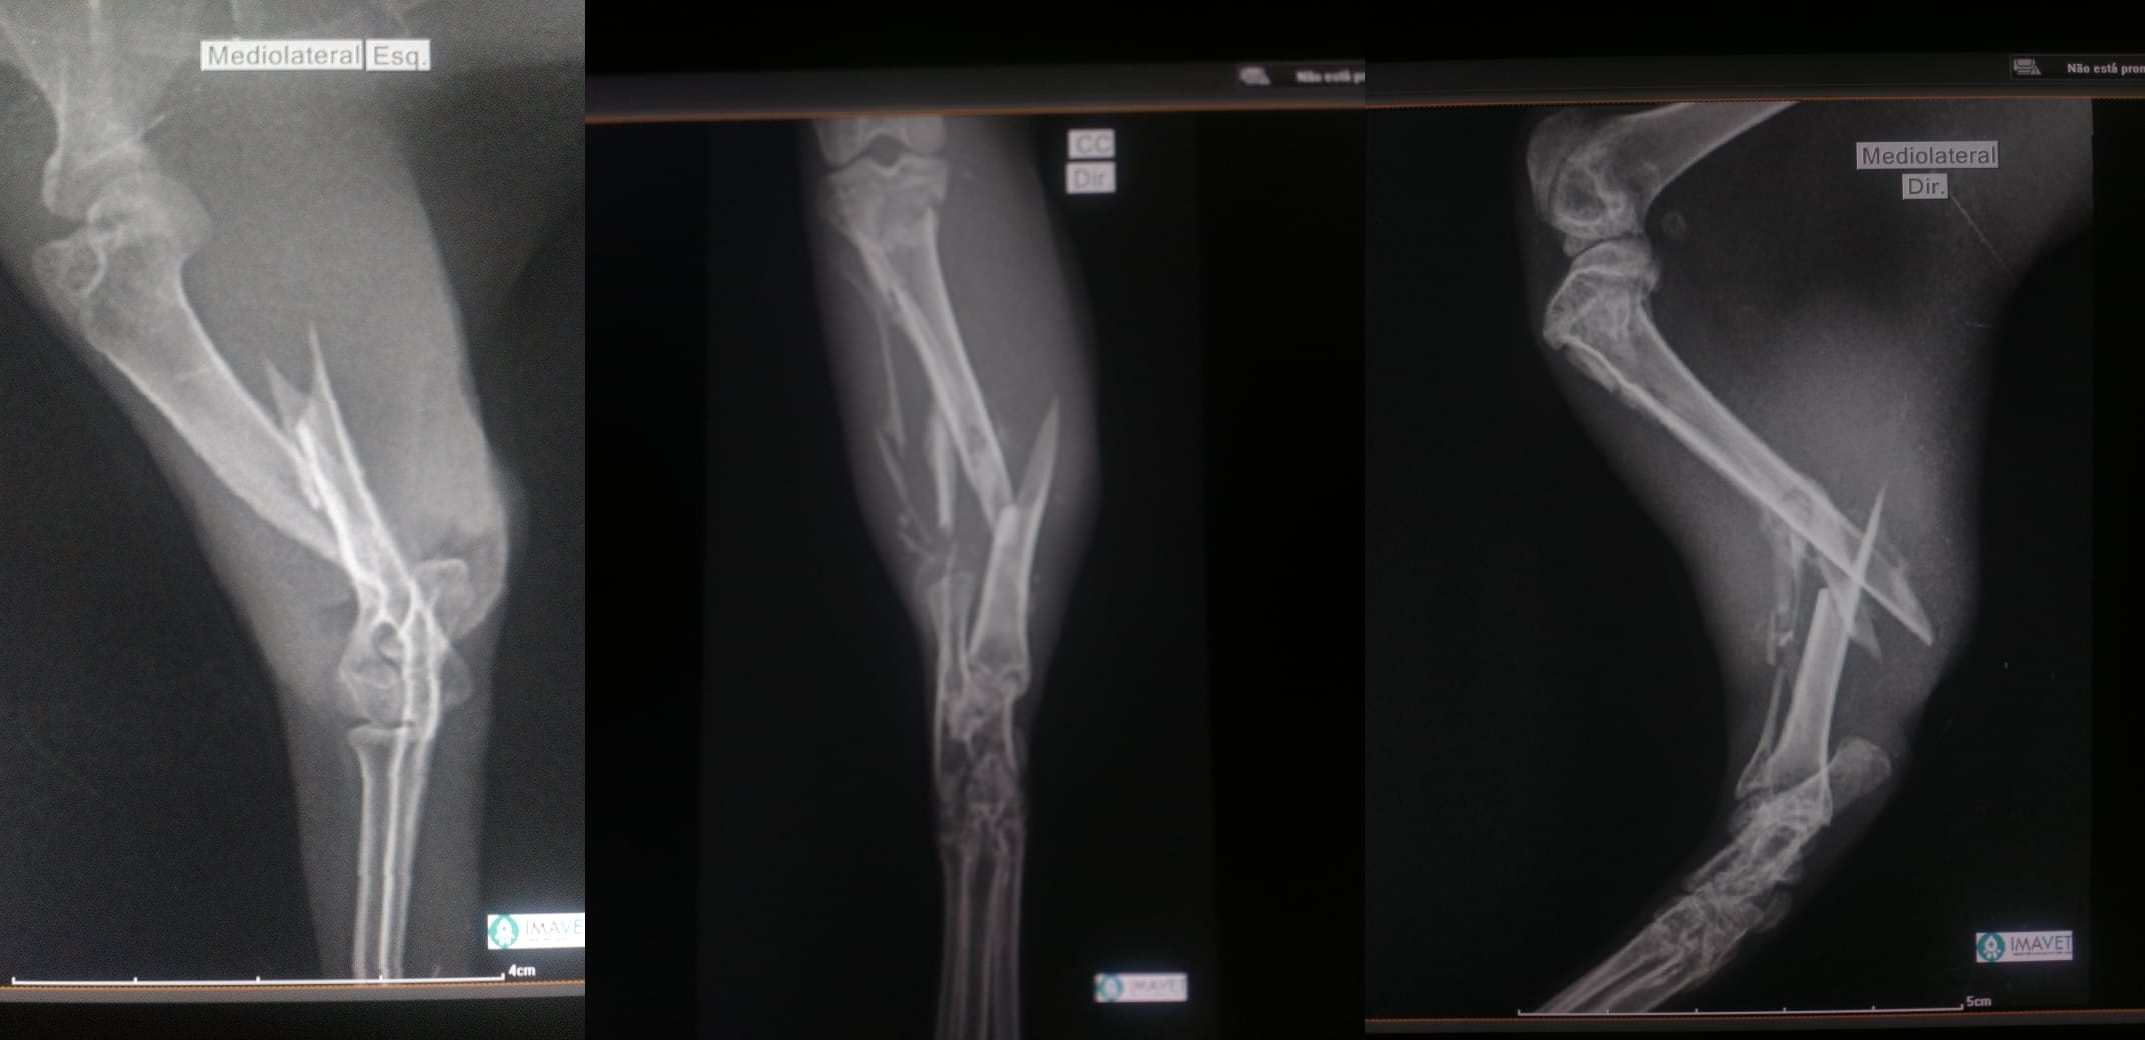

A cutia resgatada de criação ilegal necessitou de exame de raio-x, realizado no laboratório Imavet, que identificou três fraturas, uma em cada úmero (esquerdo e direito) e uma no fêmur. O veterinário ortopedista Dr. Alisson Lessa realizou as cirurgias ortopédicas necessárias em sua clínica Entre Cães e Gatos, respeitando o tempo de recuperação.